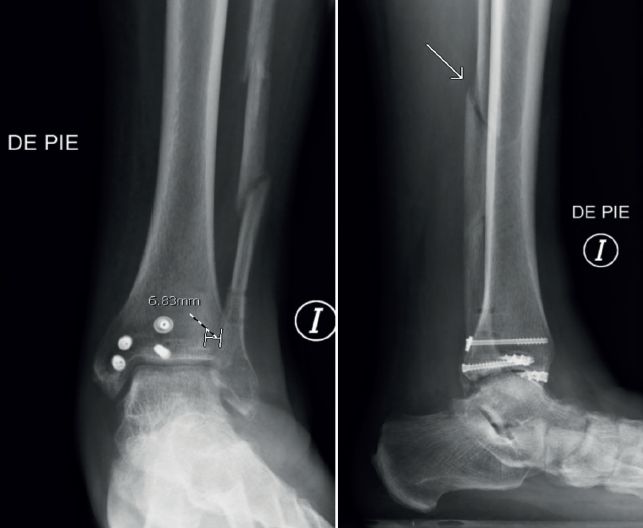

Por último, observamos 1 solo caso (caso 15) (Figura 6) de diástasis tibiofibular tras la retirada del material de osteosíntesis a las 8 semanas postoperatorias, en un varón de 55 años con una fractura segmentaria diafisaria. Revisando minuciosamente los controles postoperatorios, pudimos advertir que la fractura no estaba completamente consolidada al momento de la extracción de los tornillos suprasindesmales. Se planteó realizar una cirugía de revisión para evitar una artrosis futura, pero el paciente no accedió, al encontrase prácticamente asintomático.

Por último, realizamos un detallado análisis de las complicaciones: 3 pacientes desarrollaron cierto grado de degeneración articular en el seguimiento radiológico, sin requerir al momento de la realización de este trabajo algún procedimiento de revisión. Al igual que Mohammed et al.(27) tuvimos 1 solo caso de diástasis tibiofibular tras la extracción de los tornillos. Por ello, recomendamos, tal y como advierte Ebraheim et al.(30), retirar el implante una vez confirmada la consolidación de la fractura, sobre todo en aquellos pacientes con lesión del ligamento deltoideo.